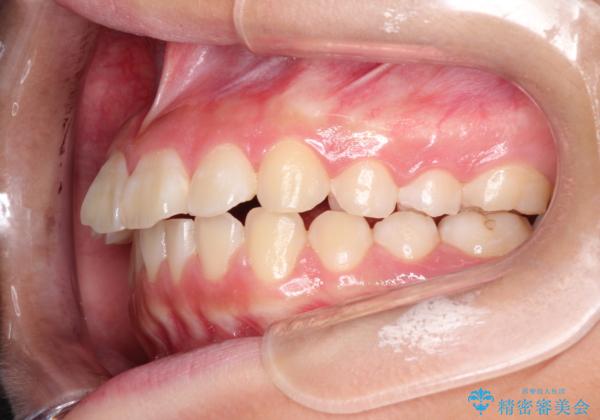

- 前歯が出ているのを主訴に来院されました。

上の前歯が前方に傾斜しており、上の前歯と下の前歯が接触していない状態でした。

上の奥歯を後方に移動させて、前歯を引っ込める計画としました。

しっかり使っていただけたので、スムーズに治療を終了することができました。